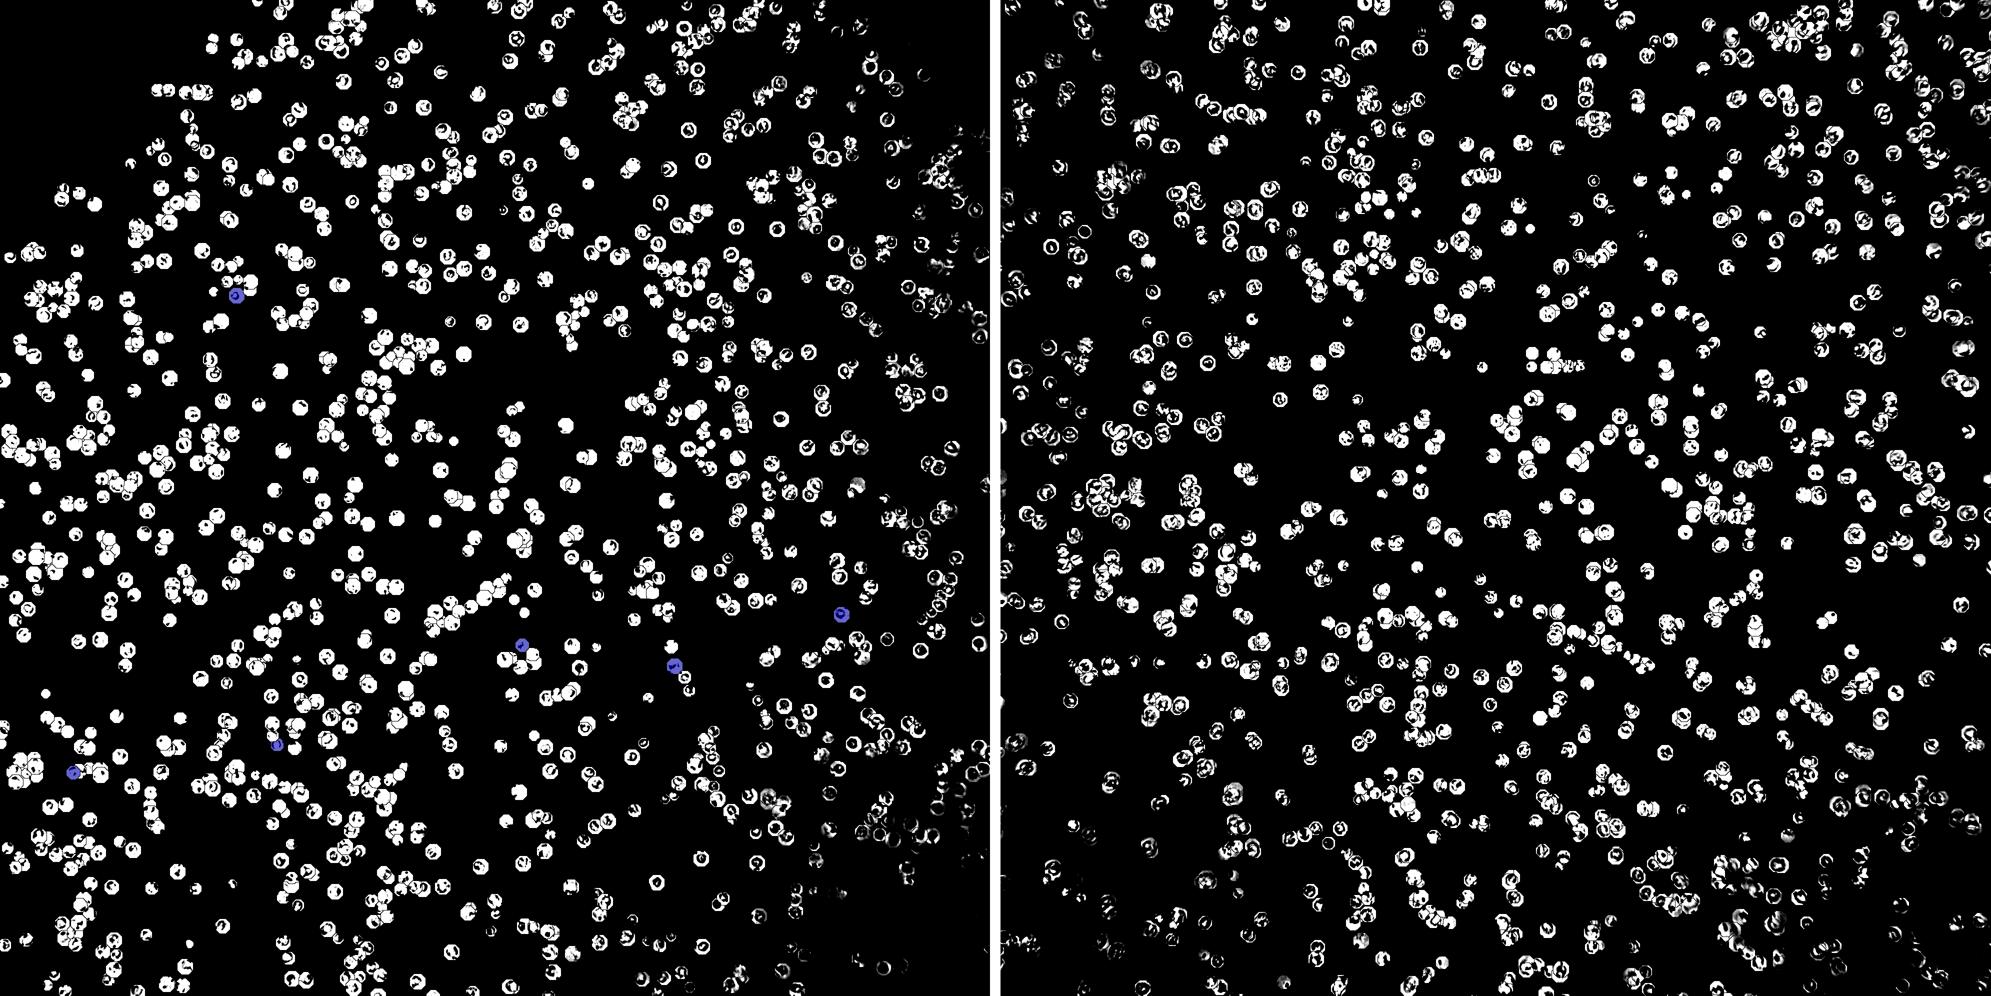

Cells labelled with CD24 CD8a

Peripheral blood lymphocytes

Inflammatory Disease

Cell populations before and after treatment